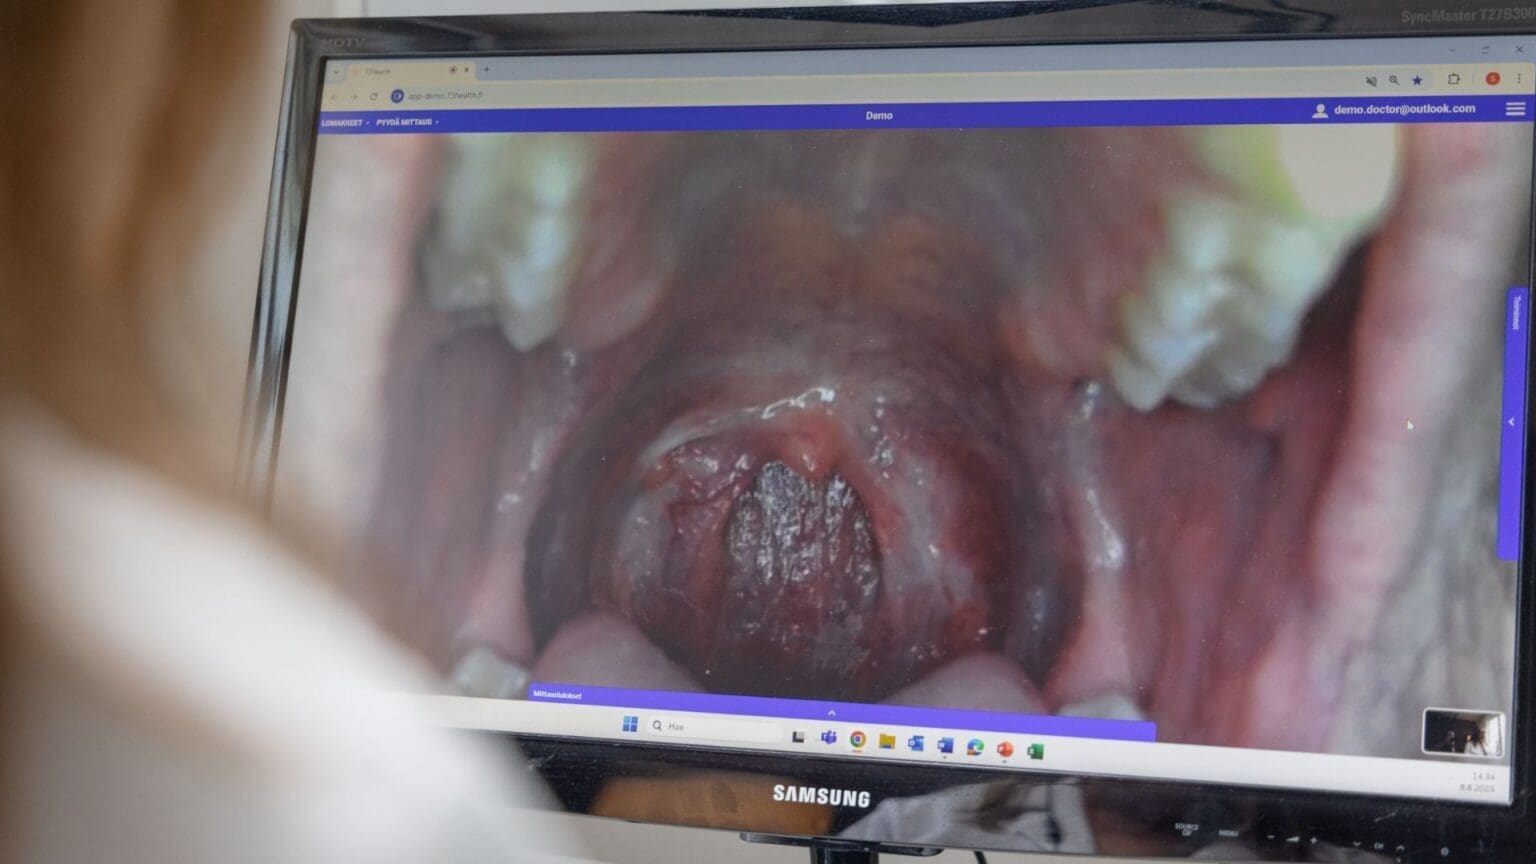

Uuden sukupolven etävastaanotto ratkaisee tämän ongelman. Potilas saa kotiinsa helppokäyttöiset tutkimuslaitteet, kuten stetoskoopin, otoskoopin ja verenpainemittarin. Lääkäri ohjaa tutkimusta etänä ja näkee tulokset reaaliajassa. Näin tutkimus onnistuu heti – ilman turhia siirtymiä, odotuksia tai päällekkäisiä käyntejä.

- Tutkimuslaitteet kotiin – Käyttäjällä on käytössään Omplyn -laitepaketti, jolla voi tutkia korvat, kurkun, ihon, sydämen ja keuhkot sekä mitata vitaaliarvot.

- Lääkäri ohjaa tutkimuksen – Esimerkiksi: “Suuntaa otoskooppi vasempaan korvaan, kuuntelen keuhkot nyt.”